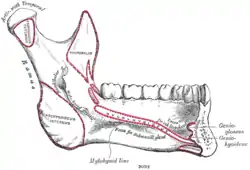

Sphenoid bone. Anterior and inferior surfaces. Mandible. Inner surface. Side view.

Mandible. Inner surface. Side view. Plan of branches of internal maxillary artery.